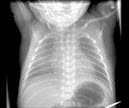

97、单项选择题

男,5岁,反复呛咳,张口呼吸,有鼾声,鼻腔分泌物多。X线检查如图所示,最可能的诊断是()

A.鼻窦炎

B.鼻息肉

C.扁桃体炎

D.腺样体肥大

E.鼻炎